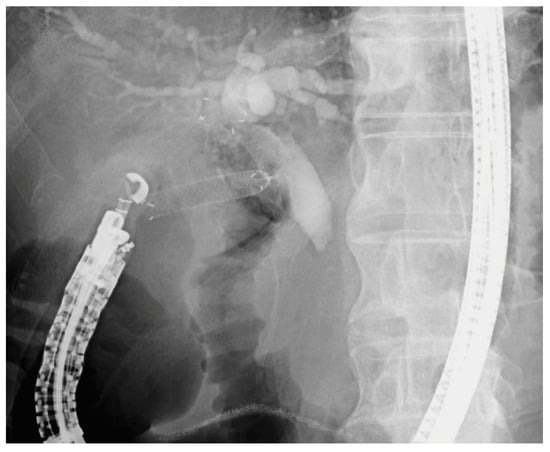

3.2. EUS-BD

3.2.1. EUS-CDS